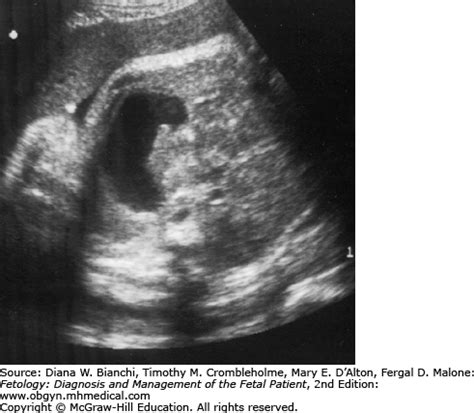

Pyloric Atresia and Stenosis | Obgyn Key